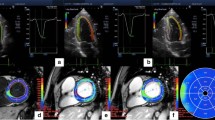

The echocardiographic abnormalities in T2DM patients seem to be related with glycemic control [12]. It is unclear whether improvement of glycemic control could reverse these structural and functional changes. The effects of a multifactorial intervention including targeting of glycemic control, cholesterol, and blood pressure on echocardiographic parameters were investigated in T2DM patients with poor glycemic control [20]. They had impaired GLS and e′ at baseline despite a normal LVEF. With reduction in both HbA1c and low-density cholesterol, relative improvement in GLS, septal e′ and E/e′ was observed after 12 months of intervention (Fig. 3). Those who had the largest decrease in HbA1c had the greatest improvement in LV systolic and diastolic function, and patients with the lowest HbA1c at follow-up had the largest improvement in GLS. No significant change was observed in LV mass index, LA volume and E/A ratio. No change was obtained in body mass index or systolic blood pressure, suggesting that glycemic control might mostly contribute to these echocardiographic changes. Although these results suggest that optimization of glycemic control improves LV systolic and diastolic function, it was a non-randomized study without placebo and had limitations. Moreover, it is unclear whether the functional improvement would lead to prevention of HF in T2DM patients.

Improvement of global longitudinal strain (GLS) after intensive glycemic control in a patients with type 2 diabetes mellitus (T2DM). Longitudinal strain images by 2-dimensional speckle tracking for the apical 4-, 2-, and 3-chamber views before (a) and after 12 months of intensive glycemic control (b) in a patient with poorly controlled T2DM. The strain throughout 1 cardiac cycle can be seen for each of the color-coded left ventricular (LV) segments (mean strain shown in white). A, The mean peak strains at baseline of − 13.3%, − 12.2%, and − 13.1%, which occur during LV ejection. The global longitudinal strain (GLS) improved from − 12.8 to − 18.2% after treatment [20]